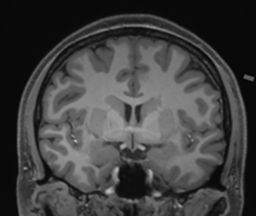

Longitudinal Tracking

Alzheimer's Disease Case Study 1

Retrospective brain volumetric analysis in a female patient diagnosed with Alzheimer’s disease at age 77 showed progressive brain atrophy over a 5-year period. The scans demonstrate both hippocampal volume loss and a clear left–right asymmetry.

PATIENT

Female patient diagnosed with Alzheimer's Disease at Age 77

Analysis period

5 years

regions of interest

Hippocampi

Inferior lateral ventricles

Age 72

Age 76

Age 77

Whole brain